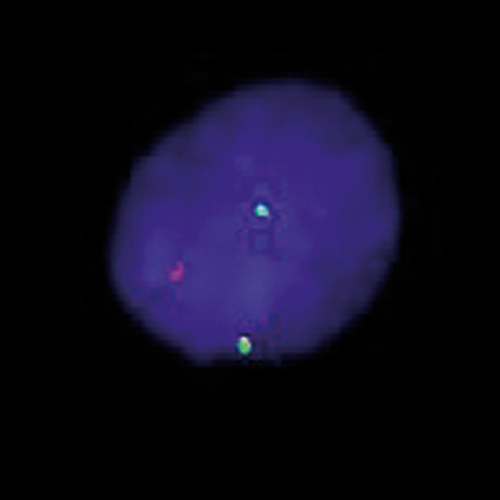

ETV6 (12p13) Break probe hybridized to patient material showing a translocation involving the ETV6 region at 12p13 (1RG1R1G). Image kindly provided by Magret Ratjen, Kiel.

ETV6 (previously known as TEL) gene is the abbreviation for -ETS variant 6- gene. It encodes an ETS family factor which functions as a transcriptional repressor in hematopoiesis and in vascular development. The gene is located on chromosome 12p13, and is frequently rearranged in human leukemias of myeloid or lymphoid origins. Also systematic deletion of the normal ETV6 allele in patients with ETV6-RUNX1 fusions can be found. The ETV6 Break FISH probe is optimized to detect translocations involving the ETV6 region at 12p13 in a dual-color, split assay on metaphase/interphase spreads and bone marrow cells.